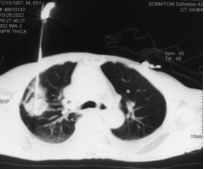

术前患者CT(肺窗) 术中精心治疗

术中肿瘤完全消融,形成椭圆型“冰球”